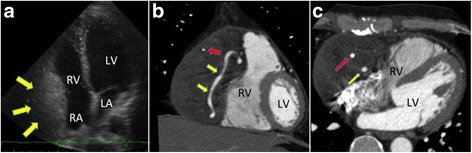

A 46-year-old man reported experiencing precordial discomfort and was referred to our department. He was a nonsmoker and had no history of any significant illness or surgery. Physical examination and electrocardiography showed no abnormal findings. Chest radiography, however, showed an enlarged right ventricular shadow, leading to a slightly elevated cardiothoracic ratio of 56%. Transthoracic echocardiography showed a mass in the pericardium, 8.0 × 4.0 cm in diameter, that compressed the wall of the right atrium and ventricle (Fig. 1a); left ventricular function was within normal limits. There was no tricuspid regurgitation or stenosis. Contrast-enhanced chest CT showed a low-density mass in the pericardium that compressed the wall of the right atrium and ventricle and encased the right coronary artery (Fig. 1b, c). The mass was relatively homogenous except for calcified nodules (Fig. 1c). No clear separation could be seen between the ventricles and the mass. Coronary angiography showed that the mass had some feeding arteries and that the proximal and mid-portions of the right coronary artery were inside of the tumor without any obstruction (Fig. 2). No other signs of coronary disease were observed. Laboratory test results, including biochemistry, coagulation, routine hematology, and serum tumor markers, were all within normal limits.

Fig. 1.

Diagnostic images. a Echocardiogram, demonstrating a hyperechoic mass (yellow arrows) adjacent to the RV. b, c Coronal (b) and transverse (c) coronary computed tomography scans, demonstrating a mass compressing the RV. The red and yellow arrows indicate calcification and the coronary artery, respectively. Abbreviations: LA left atrium, LV left ventricle, RA right atrium, RV right ventricle